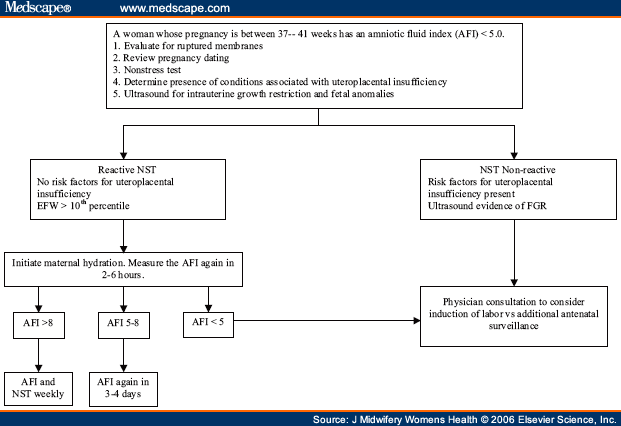

what measurements mean oligohydramnios?

AFI<5cm*

DVP (deepest vertical pocket) <2cm

*aafp says this is not great, use the other one